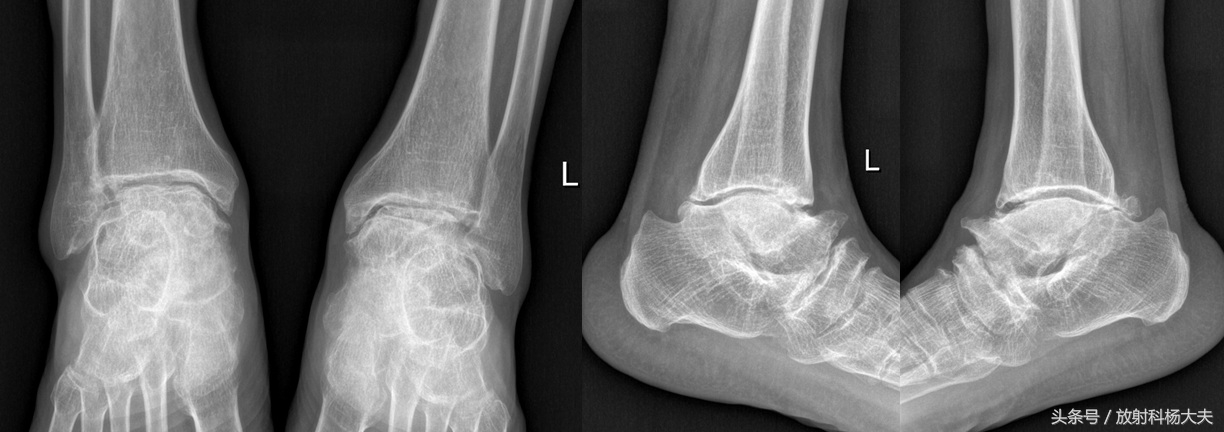

X线表现早期干骺端凹陷硬化增宽,边缘欠光整,骨骺边缘模糊凹凸不平,骨骺、干骺端提前愈合。骺线闭合后,骨长径停止发育而变短,骨端增大变形,关节面下见多发囊状骨质破坏区,关节间隙狭窄,见关节内游离体。手部:掌指骨改变常见而多发,多发生于近节及中节指骨;表现为骨端粗大,关节面欠光滑,关节面下囊状骨破坏。踝部:踝关节粗大, 胫距关节、舟距关节边缘硬化,骨刺形成。距、跟骨损害,常见且有特征,距骨颈缩短、体积小而密度高、滑车低平、头部上翘、跟骨变小而短,足弓扁平、足弓及跟骨角变小(见下图)。